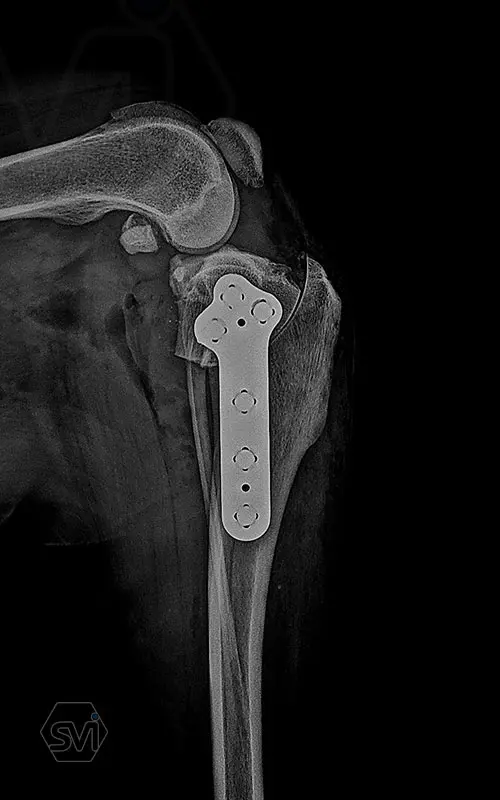

The precontoured polyaxial locking TPLO family has become complete in the smartvetimplants.com offer

Introducing the precontured polyaxial locking TPLO family, now available in all sizes:

- Mini: 2.0mm (thinner and thicker version)

- Midi: 2.4mm

- Small: 2.7mm

- Standard: 3.5mm (both in short and extended versions)

- Giant: designed for 4.0mm screws.

It has a number of advantageous features that make it stand out from standard TPLO solutions:

- well designed that follows the anatomical position and ideal hole placement

- precontoured, its use shortens the surgical time, no greater physical force is required for bending

- locking system for greater stability

- polyaxial screw insertion, the direction of screw insertion can be freely selected in a 30-degree circle while maintaining angular stability! (this is very useful to avoid driving the screw into the joint, and the temporary fixing can also be avoided with a K-wire)

- outstanding quality product, made in EU, in Hungary, and holds its own on both the European and American markets.